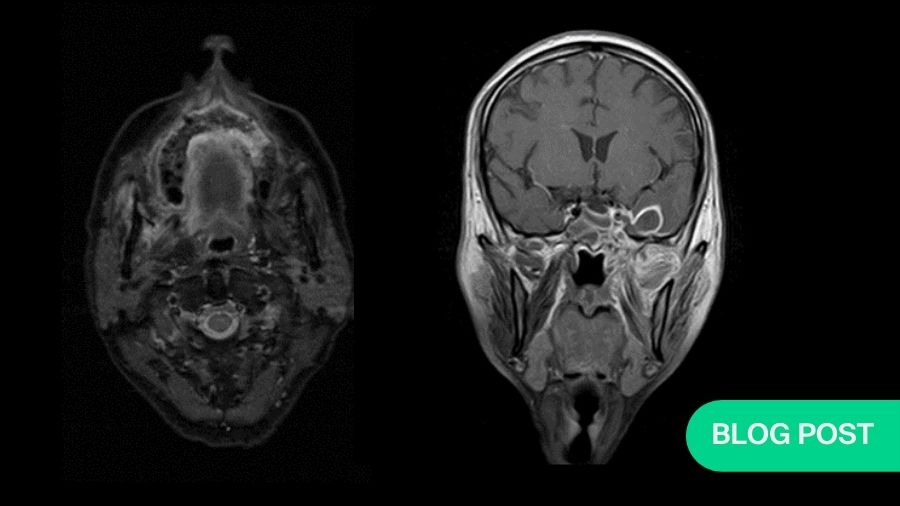

I am just getting ready to change when I see a resident running to me with case files and magnetic resonance images (MRIs) of this day’s patients. And right behind him is a patient’s relative who follows along. I go through the MRI with my ENT friend while he explains this 30-year-old patient, with cerebral abscess and both the maxillary antrum filled with gadolinium, delineating the massive involvement of complete maxillae, palate, all the paranasal sinuses, right orbit, and a cerebral abscess. I stare at the patient's relative who is now gazing at me with hope and desperation in his eyes; I am totally shaken and broken inside.

While the maxillofacial surgeons were more titled towards the contrast-enhanced CT (CECT) scans for diagnostic purposes, as we are more familiar with them, the ENT colleagues insisted on gadolinium-enhanced MRI scans of the paranasal sinuses. On routine discussion of MRIs with my ENT colleague and combining my own surgical experience with it, I observed that very often sequestration formation is a late and inconsistent finding in the palate; more often than not, there is no sequestration, yet the whole of palate was found to be dead with no architectural damage. The cause lies in the angioinvasive nature of the infection where multiple fungal thrombi block arterial supplies from various directions almost together, like guerrilla warfare against the immunologically suspended host. Hence, the only visible evidence of involvement and its extent before intervention are the MRI and surgeon’s own clinical judgement as she moves slowly towards exposure and debridement.